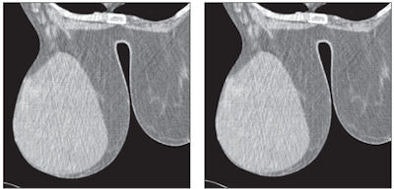

![]()  |

| Fifty-eight-year-old woman with phyllodes tumor in left breast. Dynamic MDCT scans at baseline (left) and one minute after contrast administration (right) show a large, regular lesion with early and intense enhancement in most of the breast. All images courtesy of the American Roentgen Ray Society. |